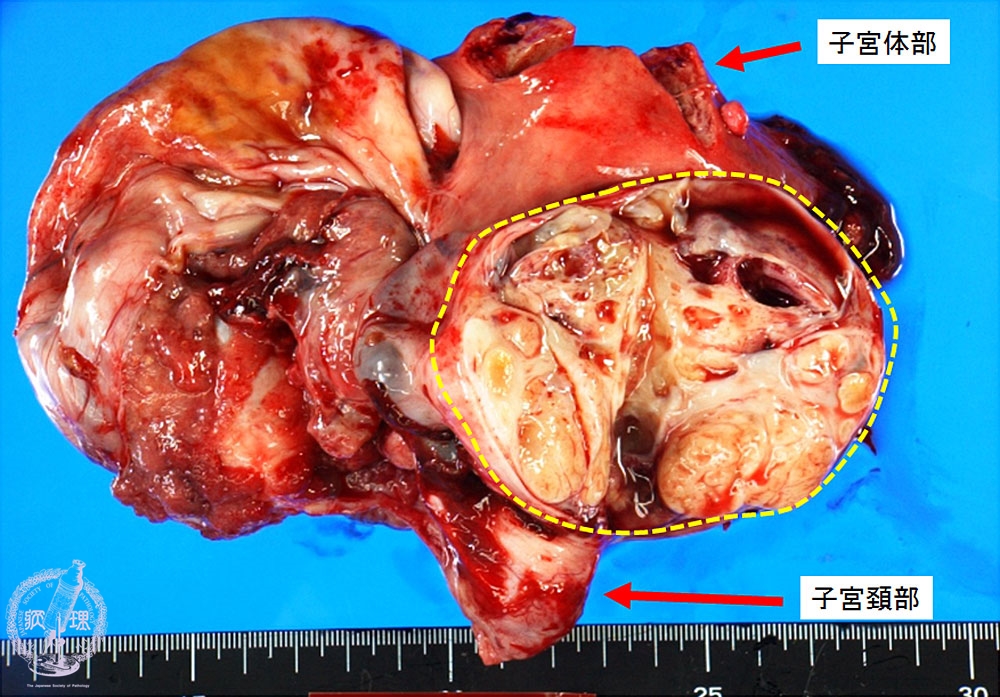

卵巣明細胞腺癌マクロ像(未固定新鮮標本)

マクロ像(未固定新鮮標本):卵巣嚢胞内には黄色調の充実性腫瘍(黄色点線)が認められる。